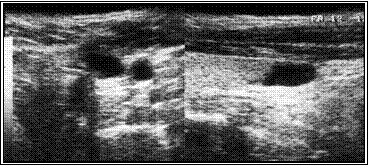

Ниже иллюстрируется клинических случай больной Л, 18 лет. При УЗИ в левой доле обнаружен кистозно-дегенерированный узел 21х9х15 мм. Кистозная дегенерация составила около 75% от объема. При диагностической тонкоигнольной пункционной биопсии дважды получены клетки фолликулярного эпитерия щитовидной железы (кубического и пролиферирующего) и элементы пунктата кистозной полости.

Расчетный объем узла ЩЖ составил 1,4 мл (= 2,1 * 0,9 * 1,5 * 0,52).

Под контролем УЗИ больной произведена пункция узла, аспирировано около 0,5 кистозного содержимого, после чего в полость образований введено 1.0 мл этилового спирта, что составило около 2/3 от расчетного объема узла.

На приведенных ниже эхограммах демонтрируется динамика регрессии в течение года.

А. Эхограмма до склеротерапии

Б. Эхограмма через три месяца после склеротерапии

В. Эхограмма через год после склеротерапии. Полная регрессия узла.